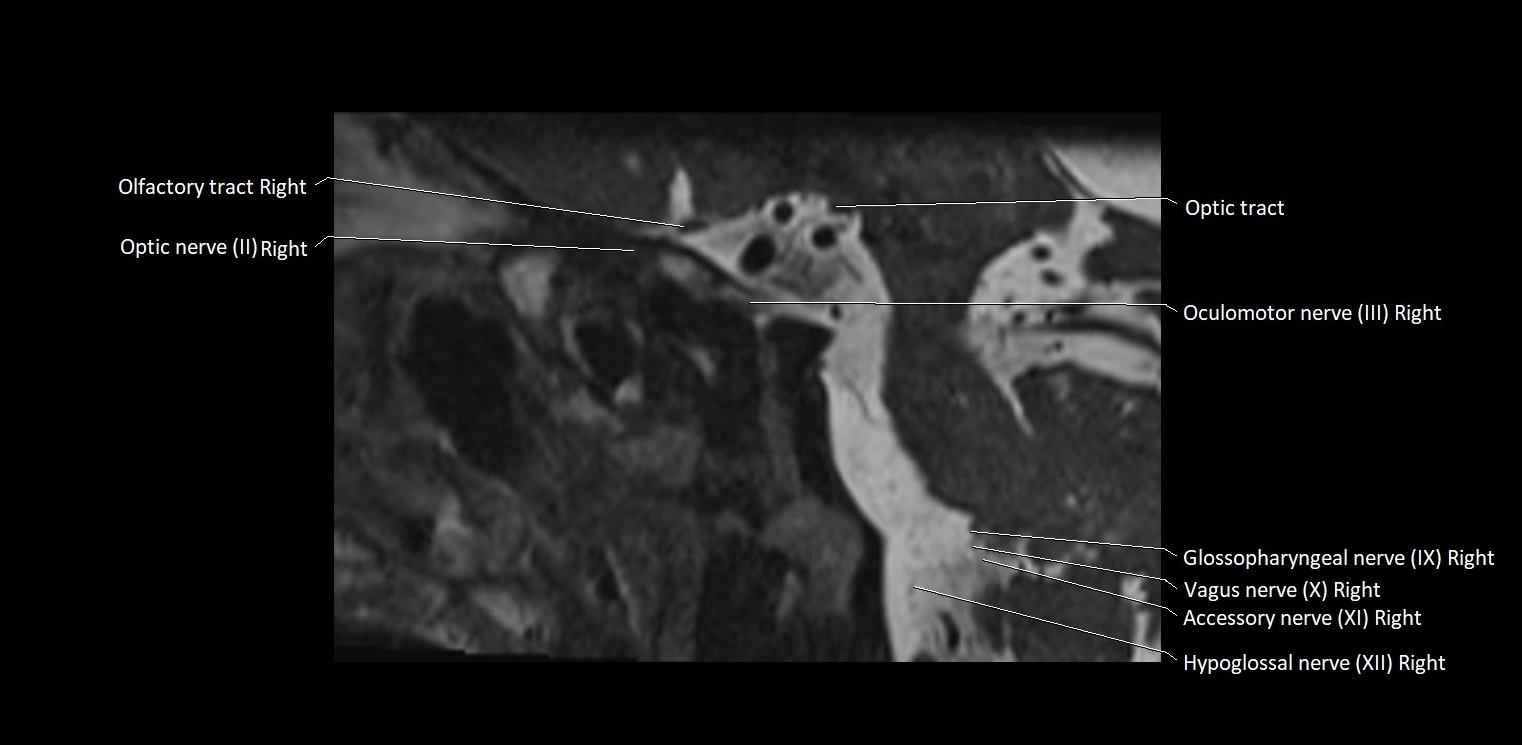

MRI images

image